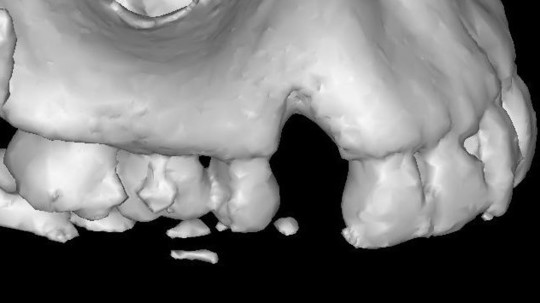

①根が割れた状態

このようにインプラント予定部位に骨がなくても骨を作る(骨造成)ことができます

治療前

骨造成して完成

インプラントができない主な原因は、インプラントを埋め込む部分に十分な骨がない場合が多く考えられます。このような場合には、不足している部分に骨を増やす治療法を行うことができます。これは高度な技術を必要とする治療法で、どの歯科医師でも実施可能というわけではありませんが、どうぞご安心ください。

当院の歯科医師は豊富な治療経験と、意欲的に学び続け習得してきた知識・技術で対応することが可能です。GBRやソケットリフトと呼ばれる、骨を増やす「骨造成」という治療のほか、歯ぐきを形成する外科手術にも対応しています。インプラントが難しいと診断されたことがある方も、諦めずにご相談ください。

インプラントは虫歯にならない素晴らしい材料ですが、欠点もあります。天然の歯に存在する『歯根膜』がありません。『歯根膜』は歯根の保護や周囲組織への栄養など、200∼300ミクロンという薄さながら大きな役割を持っています。その『歯根膜』がないため、インプラントそのものだけではなく、インプラントの周囲にも気を配る必要があります。インプラント周囲に十分に骨を作ったり、歯ぐきを強く厚くしたり、というのは、『歯根膜』がないという欠点を補うためのものです。(行う必要がない場合も多くあります)